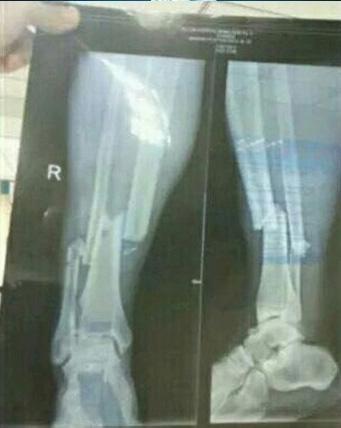

이후 병원에서 찍은 뎀바 바의 엑스레이 사진은 더 참혹했다. 왼쪽다리 경골과 비골이 완전히 부러진 것.